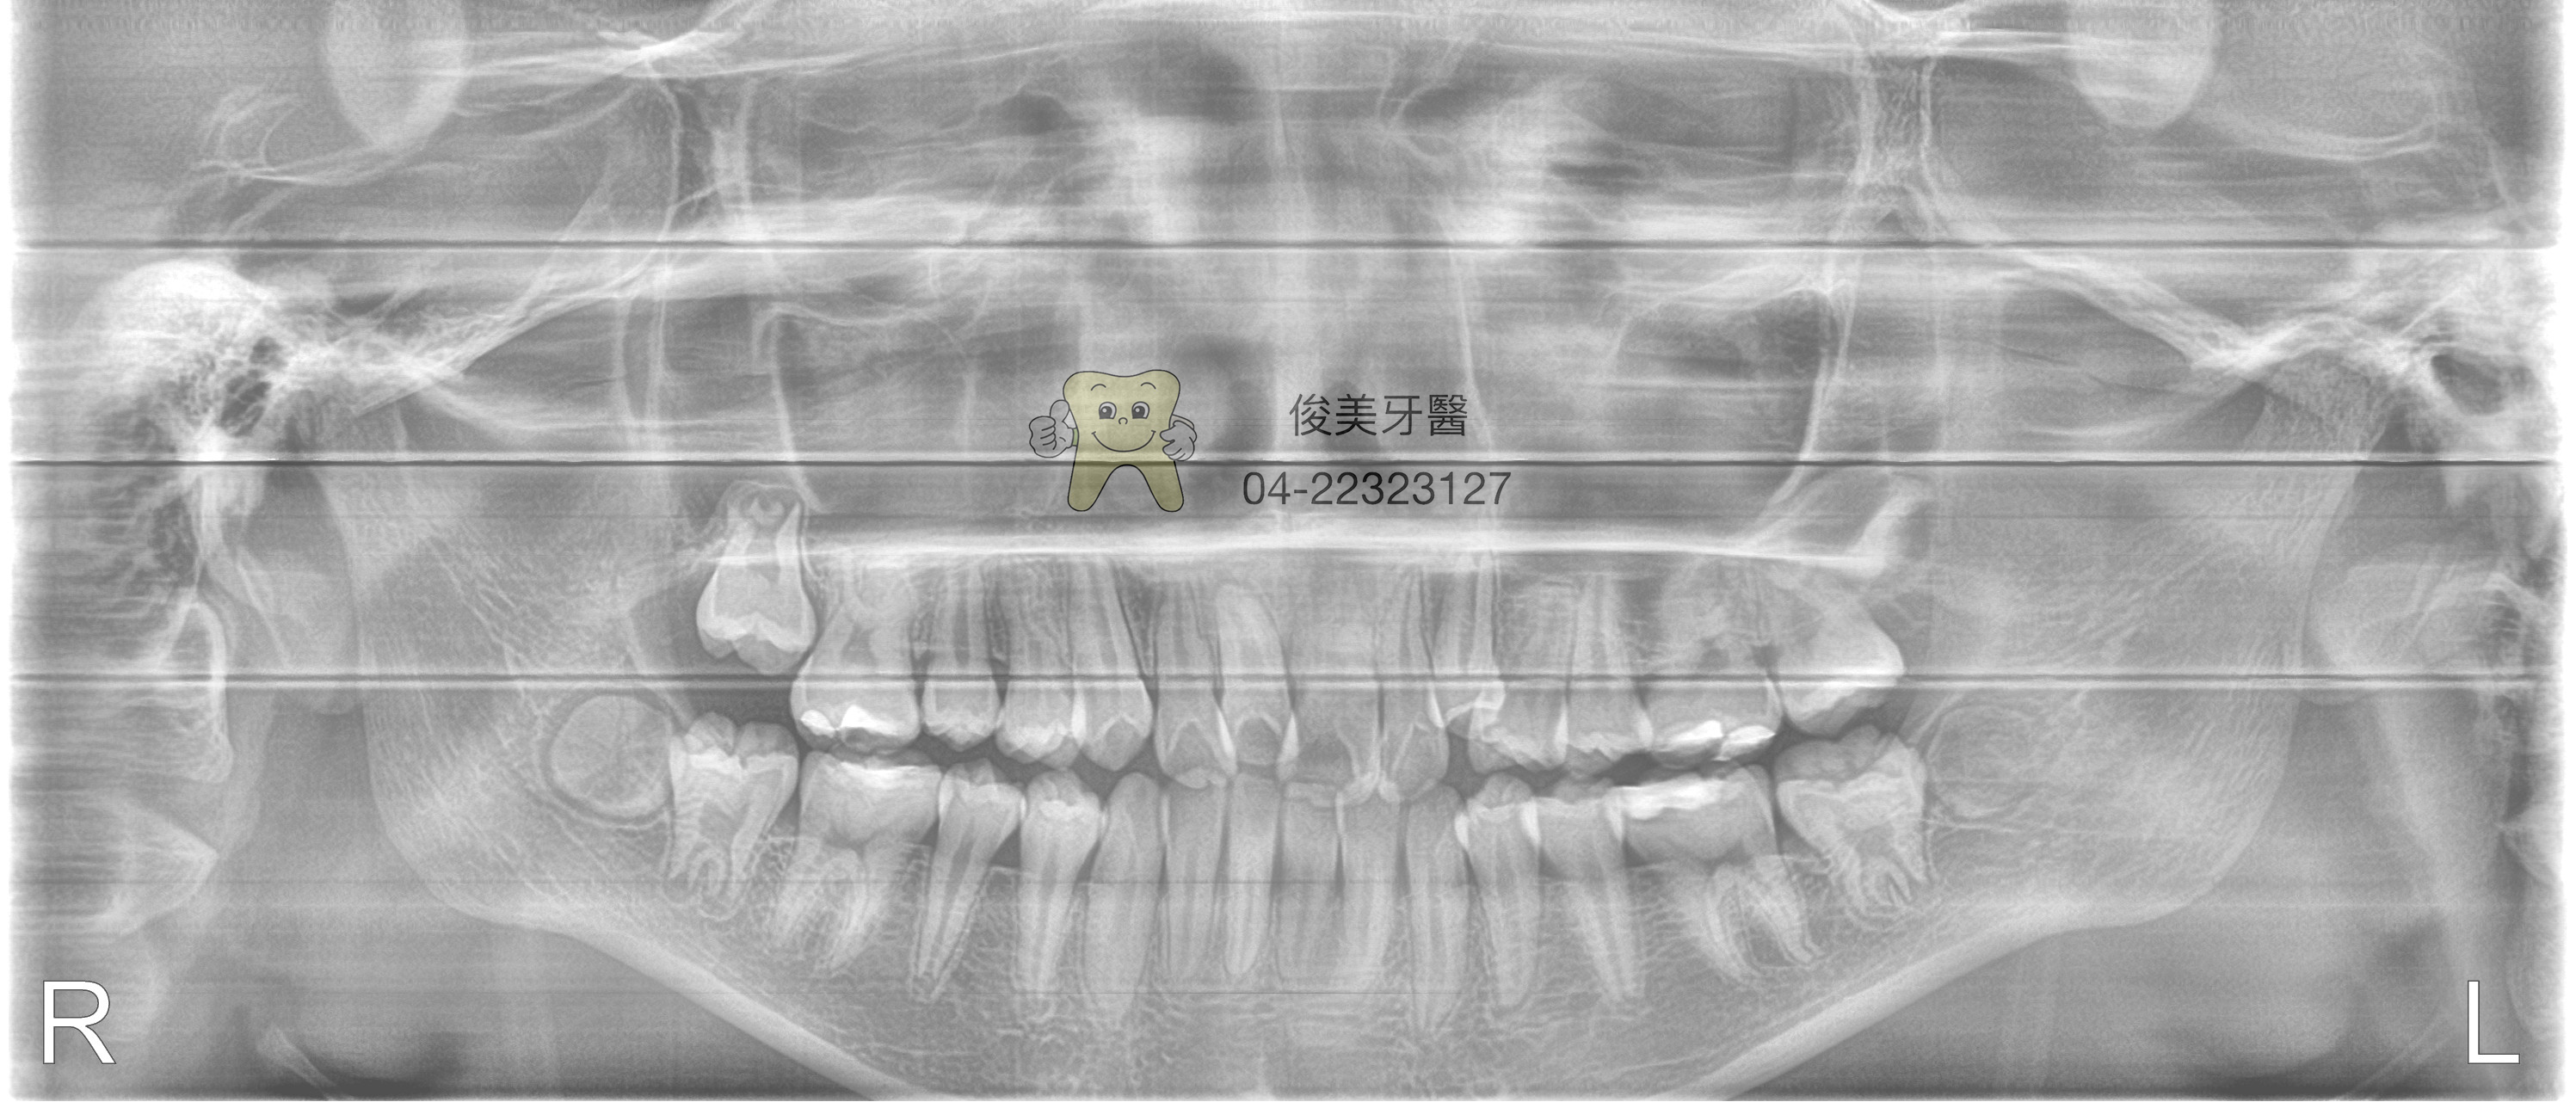

患者牙醫擁擠,不但不易清潔也不美觀,家長希望能獲得改善,但却不想要拔除好的小臼齒,經醫師評估後,

確認 可以不用拔除4顆小臼齒,做舌側矯正及傳統矯正,但必需將下顎埋伏智齒拔除,以免干擾及阻礙牙齒的

移動。